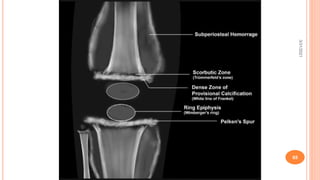

IMAGING

 Pencil thin cortex – osteopenia is the first change seen, with thinning of the

cortices.

 White Line of Frankel - the zone of provisional calcification increases in width

and opacity because of failure of resorption of the calcified cartilaginous matrix,

and it stands out in comparison to the severely osteopenic metaphyses.

 Trummerfield’s zone of rarefaction

 Wimberger’s ring sign - the margins of the epiphyses appear relatively sclerotic,

a finding termed ringing of the epiphyses, or Wimberger sign.

 Pelkan’s Spur - lateral spur formation at the ends of the metaphysis is produced

by outward projection of the zone of provisional calcification.

 Corner sign of Park –or angle sign of scurvy is a peripheral metaphyseal cleft

caused by a defect in the spongiosa and cortex adjacent to the provisional zone

of calcification.

 Scurvy line or scorbutic zone - a radiolucent transverse band adjacent to the

dense provisional zone.

 Ground-glass appearance